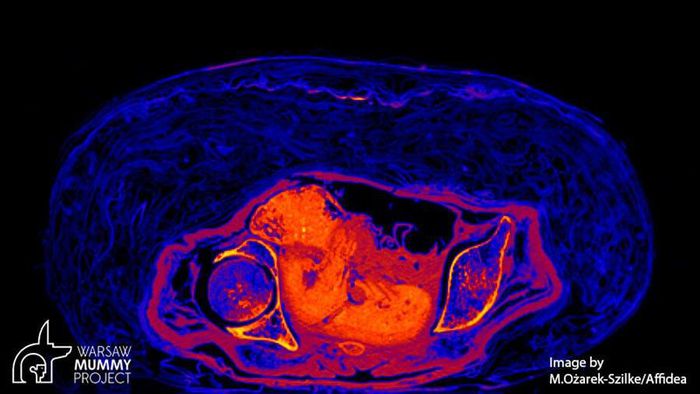

Tuy nhiên, bí mật "động trời" về giới tính của xác ướp trên được hé lộ khi các chuyên gia sử dụng kỹ thuật chụp cắt lớp vi tính vào năm 2016.

Kết quả cho thấy xác ướp không phải là của linh mục Hor-Djehuty. Thay vào đó, thi hài thuộc về một phụ nữ tử vong khi mang thai. Thai nhi đang ở tuần thai thứ 26 - 30.

Sau khi tử vong, thai phụ trên được ướp xác cùng với bào thai trong bụng. Từ đây, các chuyên gia đặt ra hàng loạt câu hỏi như: người phụ nữ này là ai? Tại sao bà được ướp xác cùng với thai nhi?...

Trước sự việc này, nhà khảo cổ học Wojciech Ejsmond thuộc Học viện Khoa học Ba Lan cho biết bào thai đã không được lấy ra khỏi bụng mẹ như trong quá trình ướp xác thông thường.

Chính vì vậy, tính đến thời điểm hiện nay, đây là xác ướp duy nhất được ướp xác với thai nhi nguyên vẹn trong bụng mẹ.